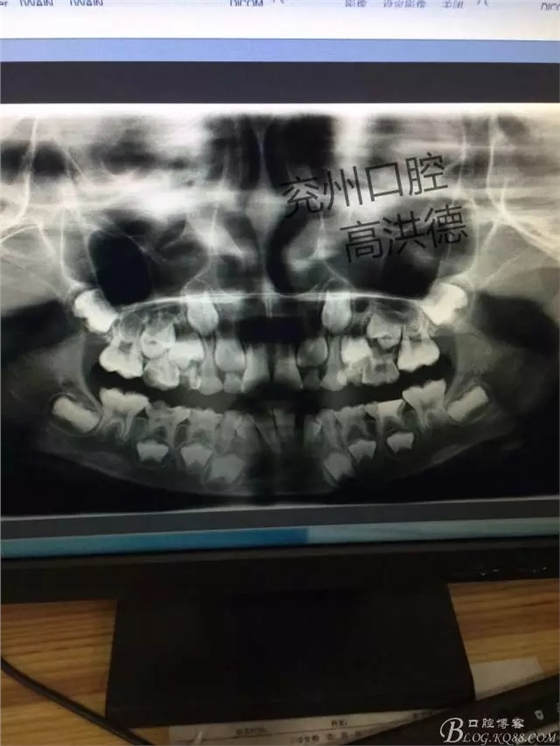

X片可見32遠(yuǎn)中移位

檢查見;患兒發(fā)育正常,神態(tài)自如,開口度正常,混合牙列,腫物位于31,32之間,32受腫物擠壓影響遠(yuǎn)中傾斜。